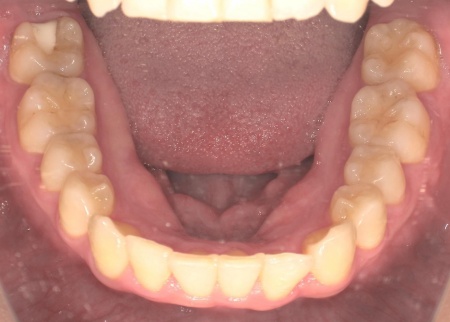

20代女性 八重歯と歯並びの乱れをマウスピース矯正装置で改善した症例

拝見したところ、歯が正しく並ぶためのスペースが不足しており、歯が重なって生えてしまう叢生(そうせい)の状態が全体的に見られました。

特に上下の糸切り歯が外側にずれている、いわゆる八重歯が目立っています。

矯正治療終了後、歯並びの後戻りを防ぐための保定装置を装着していただきました。

経過観察を行い問題がないことを確認して、治療を終了しました。